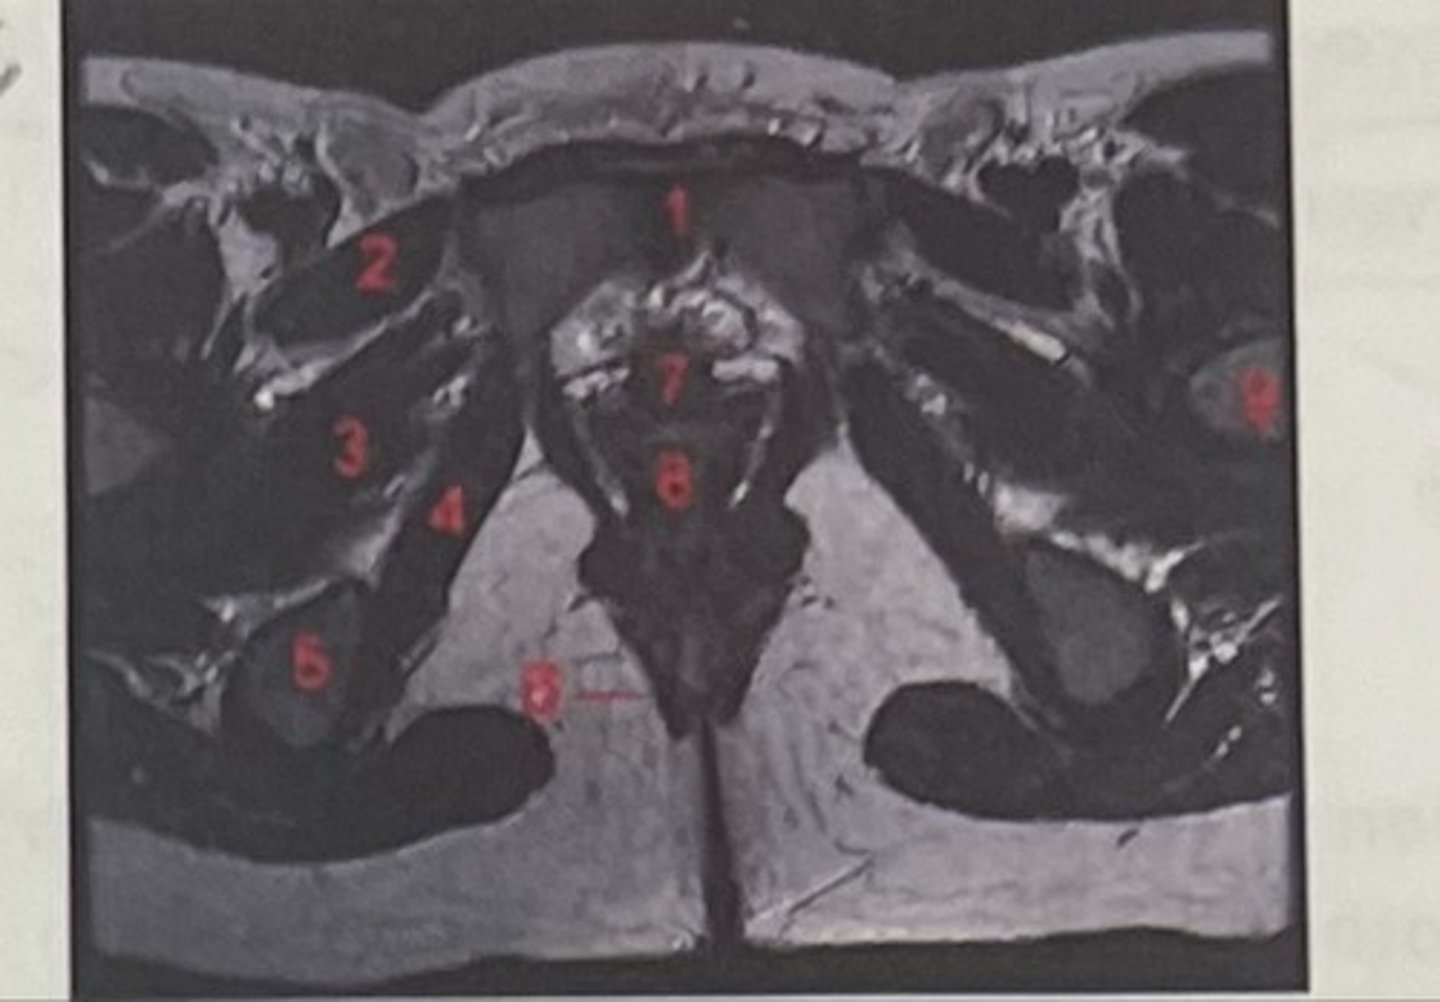

pubic symphysis

What is 1

Pectineus

What is 2

Obturator externus

What is 3

obturator internus

What is 4

ischial tuberosity

What is 5

external spincter

What is 6

Urethra

What is 7

Vagina

What is 8

Femoral nerve

What is 9